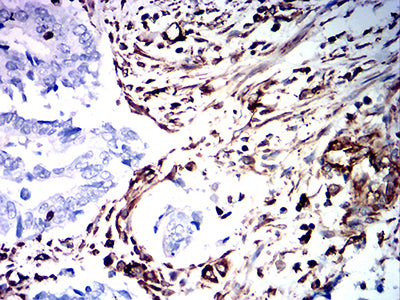

Immunohistochemical analysis of paraffin-embedded human cervical cancer tissues using VIM mouse mAb with DAB staining.

Immunohistochemical analysis of paraffin-embedded human rectum cancer tissues using VIM mouse mAb with DAB staining.